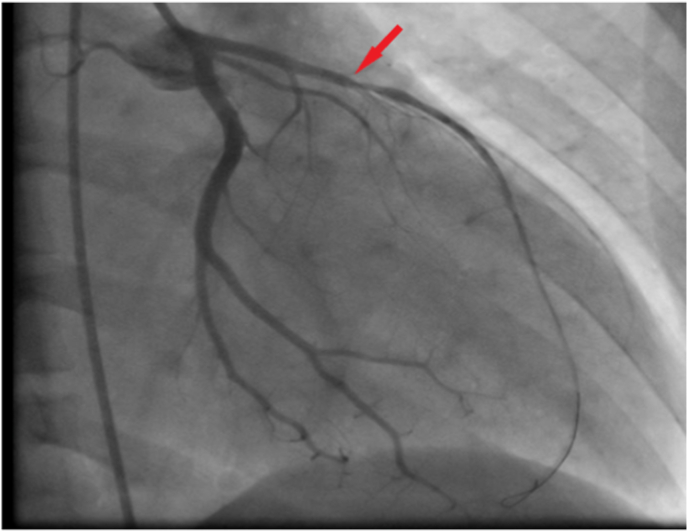

Coronary angiography was performed and a significant stenosis in the middle segment of the left anterior descending artery (LAD) was noted (Fig. 3). A Percutaneous Coronary Intervention (PCI) of the LAD was realized with the implantation of a new generation-stent (Fig. 4).